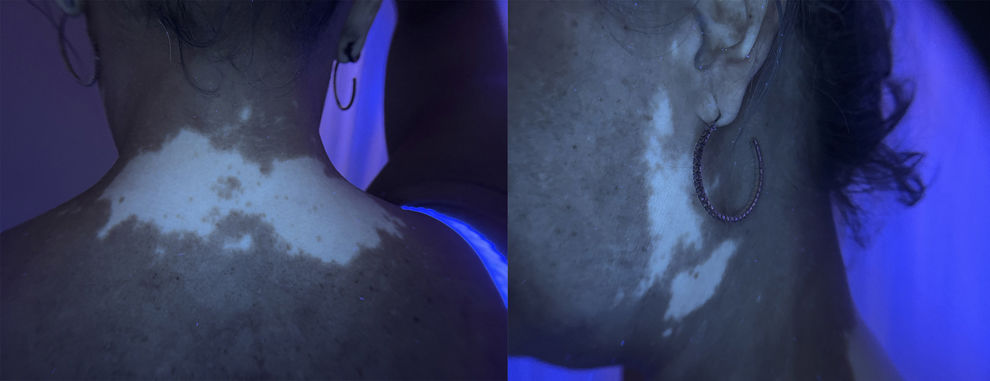

Physical examinationExamination revealed acral macules with well-defined borders located on the posterior neck, as well as periocular, frontal, and preauricular regions of the face (Figs. 1 and 2). The lesions became more evident under Wood's lamp examination (Fig. 3).